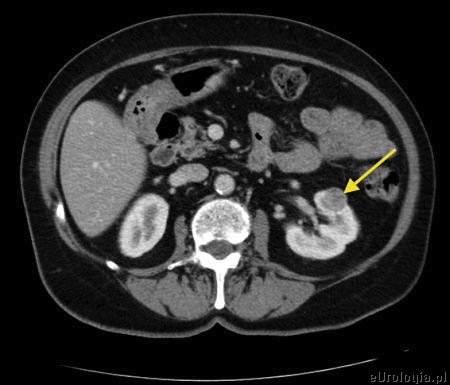

Guz nerki - enukleacja

Mam 58 lat i 3 tygodnie temu w USG brzucha wykryto u mnie guz nerki średnicy około 2 cm. Obecność guza w nerce potwirdziło badanie KT jamy brzusznej. Urolog, który będzie mnie operował twierdzi, że guz jest mały i dobrze zlokalizowany więc spróbuje zrobić enukleację - oszczędzi mi nerkę. Czy enukleacja guza nerki jest zabiegiem bezpiecznym? Czy nie lepeiej usunąć od razu całą nerkę.

W przypadku małych guzów nerki, zlokalizowanych brzeżnie optymalnym sposobem leczenia są operacje polegające na usunięciu guza z oszczędzeniem nerki. Wiele badań dowiodło, ze